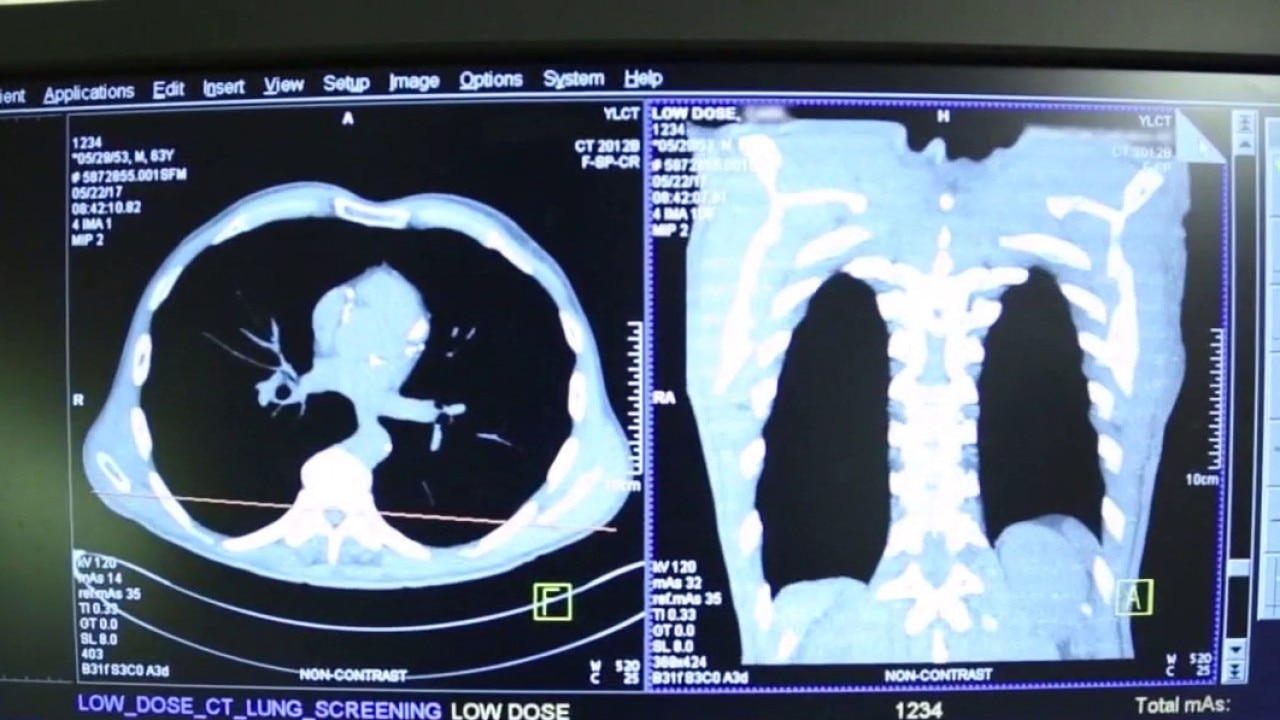

Early detection for lung cancer

Lung cancer is now the leading cause of cancer deaths. In addition, the rates are increasing in young people who have never smoked before.